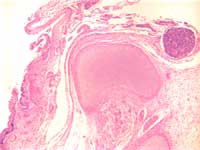

Figure 3: Incomplete formation of

vertebral body with primitive neural

tissue in continuity with squamous

epithelium.

A lumbrosacral myelomeningocele is confirmed. The vertebral body is incomplete at the point of the defect. The squamous epithelium is not continuous overlying the vertebral column; instead there is immature neural tissue in continuity with the squamous epithelium.